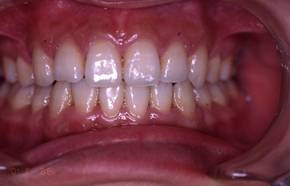

インビザGOによる矯正症例1 16歳男性

マウスピース矯正開始前。右上犬歯が内側にありました

前から見たところ